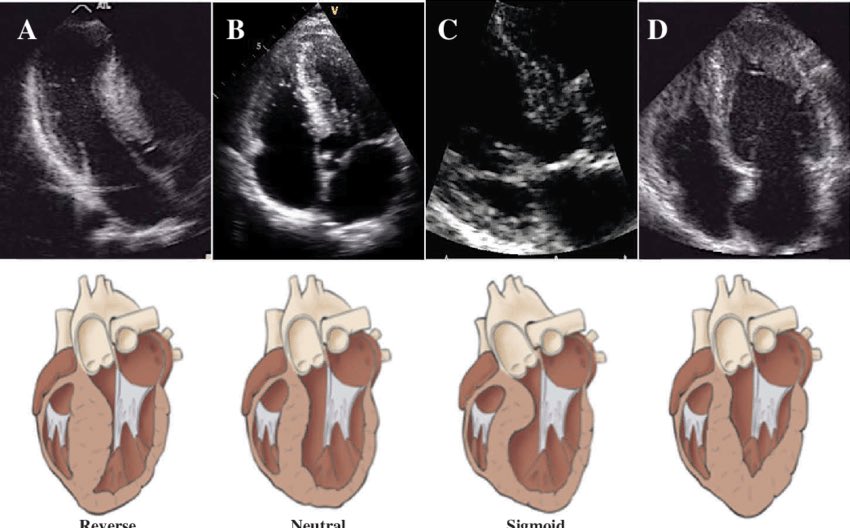

HCM is often ventriculoseptal➡️predisposes to LV outflow tract obstruction +/- SAM of mitral valve (due to Venturi effect/abnormal papillary seating).